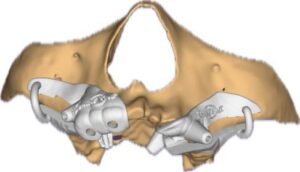

Rehabilitating a severely atrophic maxilla presents one of the most complex challenges in implant dentistry. Traditional implant placement is often compromised due to insufficient bone volume, especially in the posterior maxilla.

In such cases, the strategic use of pterygoid and zygomatic implants, combined with conventional anterior and molar implants, offers a predictable and minimally invasive solution. This blog outlines a step-by-step protocol for guided placement of zygomatic and pterygoid implants using bone-supported guides and periosteal pin registration.

The hybrid approach integrates flapless guided pterygoid implants, conventional anterior implants, and then bone supported zygomatic implants.

This method ensures optimal stability, reduced surgical trauma, and immediate functional loading when planned meticulously. The key lies in precise guide stabilization and sequential osteotomy using bone-supported templates.

Guided placement of zygomatic and pterygoid implants, when combined with conventional molar and anterior implants, offers a robust solution for rehabilitating the severely atrophic maxilla.

This protocol minimizes surgical trauma, enhances accuracy, and supports immediate loading. With careful planning and execution, clinicians can restore function and esthetics even in the most challenging cases.